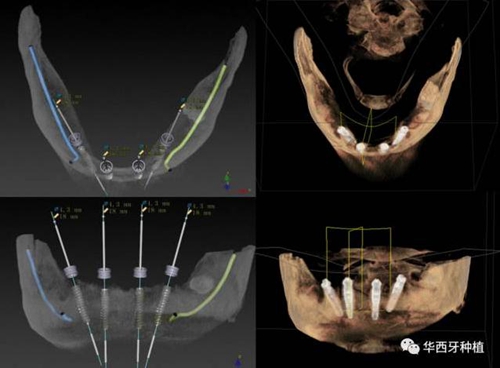

對于傳統(tǒng)的all-on-four術(shù)式,吳教授加入了微創(chuàng)的指導(dǎo)思想,設(shè)計時同樣加入數(shù)字化三維重建與修復(fù)一體化設(shè)計,增加了手術(shù)的可控性,同時極大減輕了患者的創(chuàng)傷程度,縮短了修復(fù)周期。

吳教授提到了使用數(shù)字化建模與導(dǎo)板的聯(lián)合應(yīng)用,不僅可以從設(shè)計上降低修復(fù)難度,便于在修復(fù)為導(dǎo)向的設(shè)計中種植體方向的確定,同時可以加入微創(chuàng)的手術(shù)方法,減輕術(shù)中創(chuàng)傷。